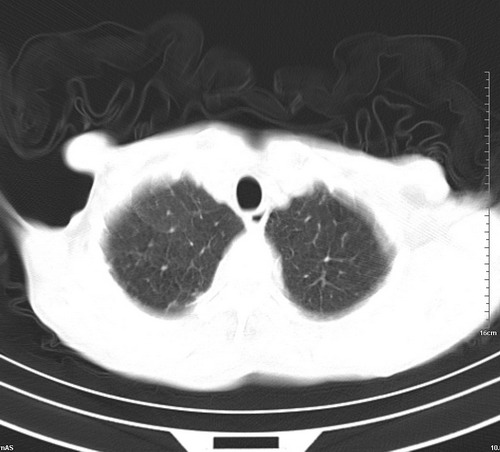

中后纵隔占位,气管、食道受压、变形、移位。恶性可能性大。

考虑:中后纵隔转移瘤可能性大,主动脉硬化。

1 气管旁、隆突下淋巴结明显肿大,肝左叶外侧段低密影,都考虑转移。

纵隔淋巴结肿大,考虑转移而来

肺癌,纵隔淋巴结转移,肝左叶病变考虑为转移病灶。

后中纵隔团块影,伴气管、食道受压移位,首先考虑转移瘤,肝s5段低密度灶。建议增强检查,另外其结肠是否有问题请提供,右肺部分肺叶局限含气增多,考虑局限肺气肿。

建议强化检查,考虑纵隔型肺癌,小细胞可能性大。

后中纵隔淋巴结肿大,首先考虑转移瘤。